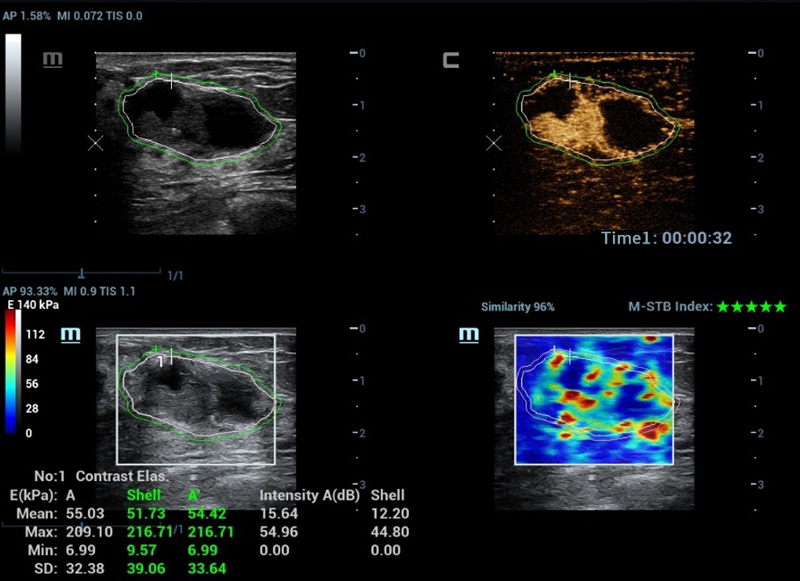

M-Reference C&E

CEUS e share wave insieme svelano il mondo dell'ecografia multiparametrica

Strumenti di analisi multiparametrica M-Reference

M-Ref. C&E

M-Ref. C&E tumore maligno al seno

M-Ref. C&E supporta la visualizzazione del contrasto e della STE in un unico piano per una valutazione comparativa della perfusione e dell'elasticitĂ .

Nuova analisi quantitativa CEUS

Nuova QA CEUS tumore maligno al seno

La curva tempo-intensitĂ offre un'analisi quantitativa dell'imaging CEUS. La Nuova QA CEUS fornisce strumenti di analisi quantitativa all'avanguardia per la valutazione dei tumori e la ricerca clinica.